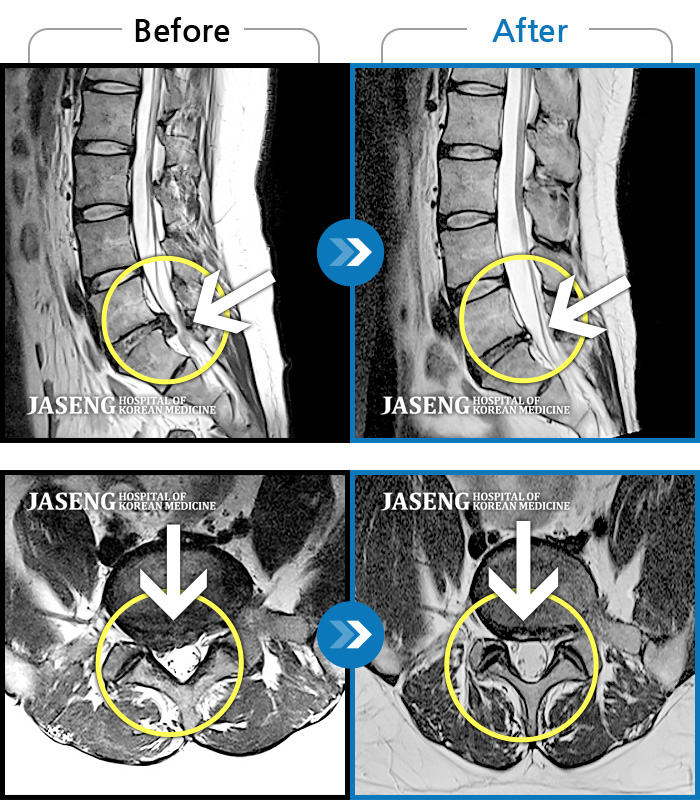

MRI 치료사례

서서 움직일 때, 앉았다 일어날 때 허리 및 우측 다리 통증